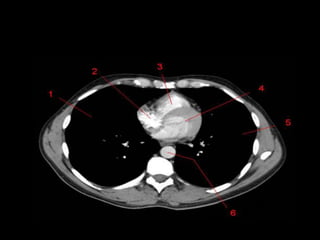

Mediastino Médio

• Pericárdio e seu conteúdo, arco aórtico e as

grandes artérias proximais, as artérias e veias

pulmonares centrais, traquéia, brônquios

principais e linfonodos.

• Nervo frênico e vago não são visíveis a TC.

• Janela Aortopulmonar

– Tecido adiposo, linfonodos, ligamento arterial e

nervo laringeo recorrente.